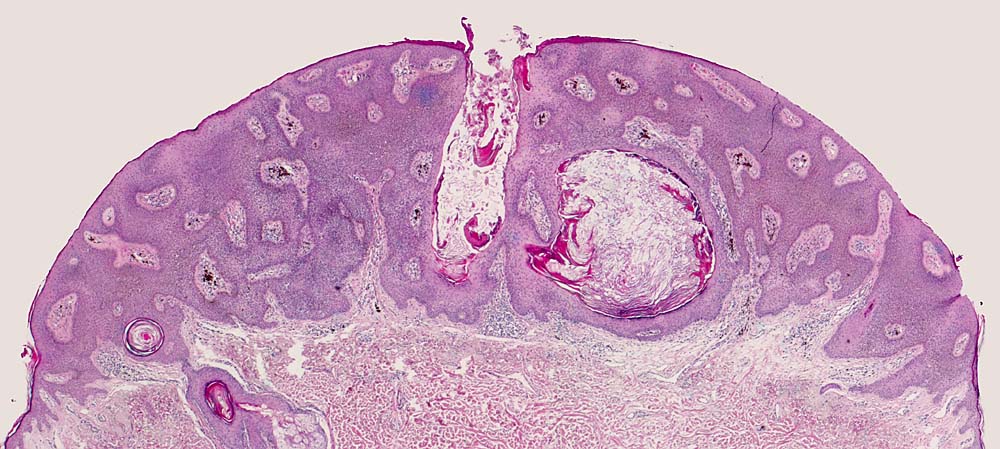

Histologie: Die grosse makroskopische Vielgestaltigkeit widerspiegelt sich auch in einer variablen Histologie. Unterschieden werden mehrere histologische Subtypen der seborrhoischen Keratose: Hyperkeratotischer Typ ( 3435), akanthotischer Typ (Kurspräparat), klonaler Typ ( 7284)( 7285), irritierte seborrhoische Keratose ( 3353)( 3356). Typisch für seborrhoische Keratosen sind umschriebene Wirbelbildungen von Tumorzellen, sogenannte squamous eddies ( 8065). Der retikuläre Typ ( 7838) entwickelt sich in chronisch UV exponierter Haut meist im Gesicht und geht oftmals hervor aus einer solaren Lentigo ( 7839).